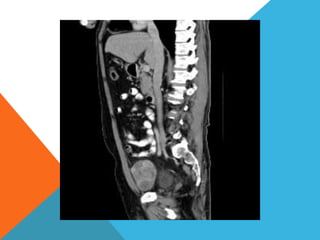

El paciente presentó síntomas de sangrado digestivo y pérdida de peso. Exámenes revelaron gastritis crónica asociada a H. pylori. Un tumor fue descubierto en una colonoscopia normal. La cirugía removió un tumor fibroide solitario, una rara neoplasia mesenquimal que usualmente crece lento y tiene bajo potencial de malignidad. El pronóstico después de la remoción quirúrgica es generalmente bueno.